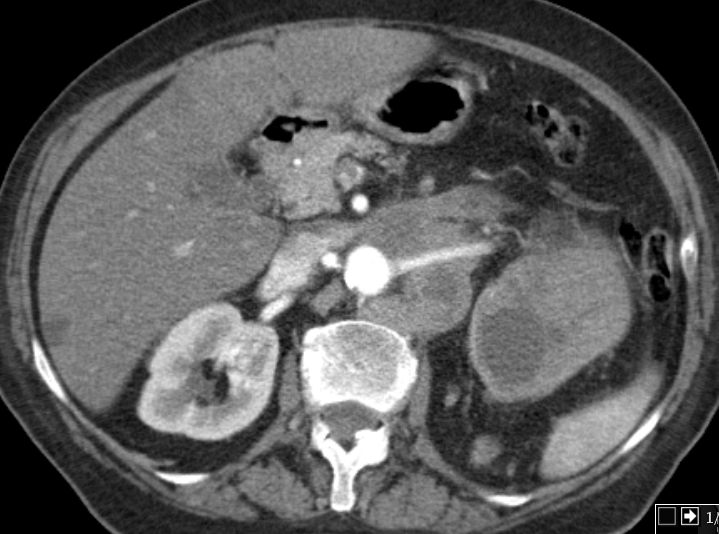

Entdifferenziertes Urothelkarzinom des rechten proximalen Harnleiters pT4 G3 L1

Doppelniere links. Im oberen Anteil Hydroureter und Hydropyelons mit Wucherungen eines schlecht differenzierten Urothelkarzinoms mit Plattenepithelmetaplasie, infiltriert das umgebende Fettgewebe.G3. pT3, pN3 (2/3, 1 Lymphknoten mehr als 5 cm) L1. V0. Das CT zeigt den Nierenbeckentumor und eine Lymphknotenmetastase medial des erweiterten Ureters.

Der stark dilatierte Ureter links im kleonen Becken.